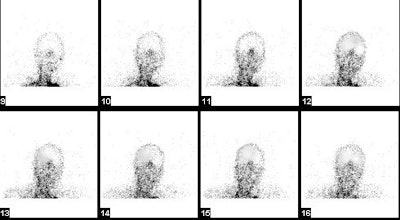

Brain death exam: The flow images demonstrated absent intracerebral flow, no sagittal sinus activity, and a hot nose sign- these findings are consistent with brain death.. |

Brain death exam- patient not dead: The flow images demonstrated intracerebral flow which was somewhat asymmetric. Later images revealed activity in the sagital sinus. A tourniquet had been placed around the skull to decrease scalp acitivity, but some scalp activity can still be seen. There is no "hot nose" sign. The exam indicated that the patient was not brain dead. |